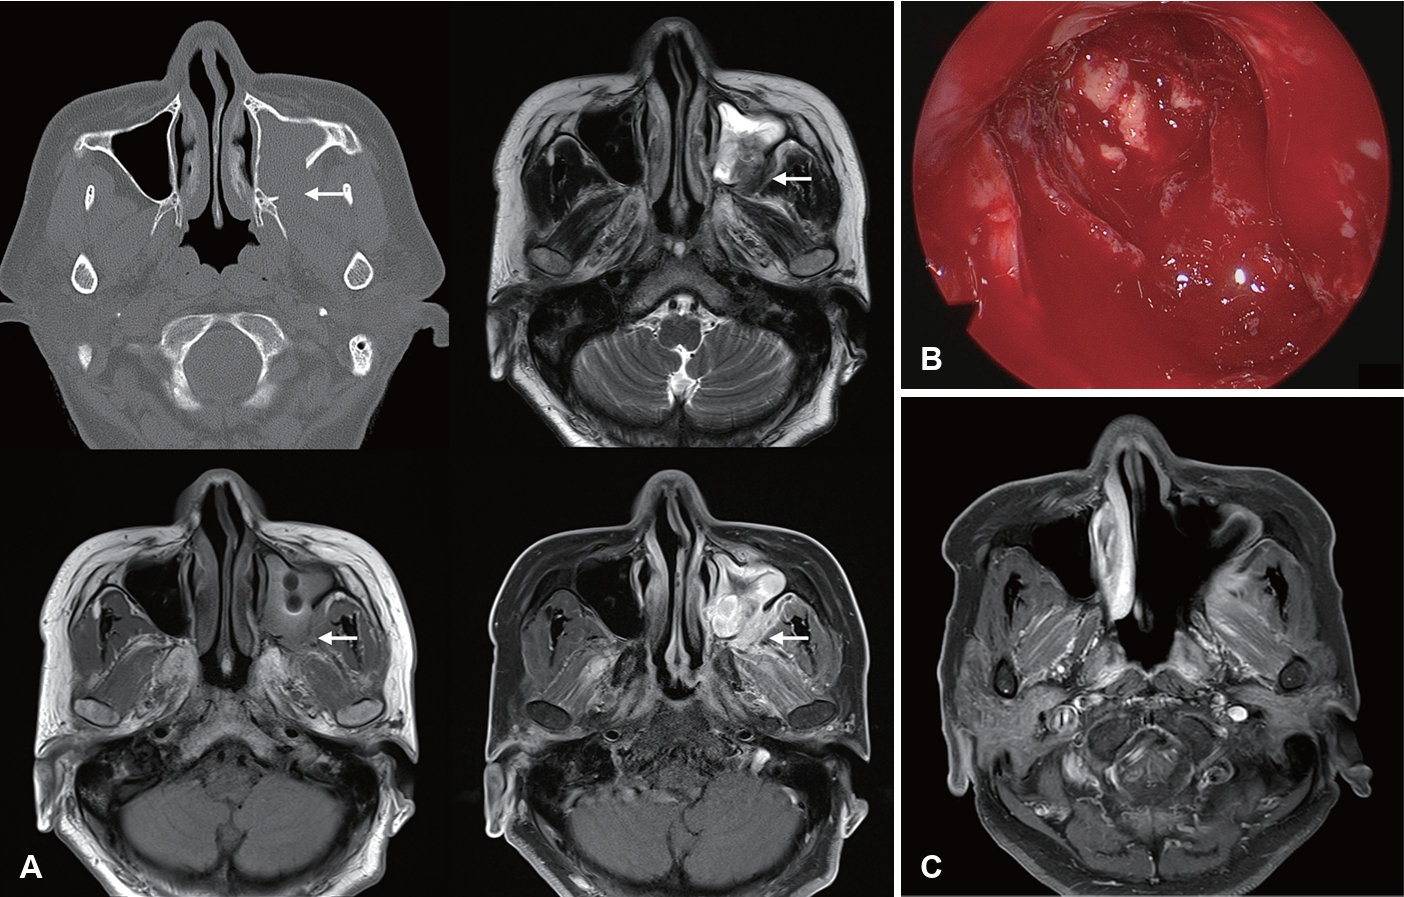

Gadolinium-enhanced MRI (Gd-MRI) has emerged as a superior modality for evaluating IFRS. The “black turbinate sign” of sinonasal tissue lacking contrast enhancement on MRI was first described to correspond to devitalized mucosa from angioinvasive hyphae [54]. However, it should be noted that nonenhancing portions of the turbinate are observed in 30% of patients without IFRS, especially in the posterior portion of inferior turbinates. Non-enhancing turbinates in immunocompetent patients retain peripheral (likely normal) mucosa enhancement and thin septa, which are key features distinguishing pathologic black turbinates from infiltrative nonenhancing lesions (IFRS), which exhibit infiltrative non-enhancement extending to adjacent structures without a smooth, thin enhancing margin [55]. MRI had a higher sensitivity than CT for diagnosing AIFRS with similar specificity, PPV, NPV, and accuracy, and LoCE on MRI showed 76.5% agreement with endoscopic mucosal findings. Therefore, MRI is more sensitive than CT in detecting early changes of AIFRS and is an appropriate initial diagnostic method when AIFRS is suspected, given suspicious endoscopic findings [52]. In 2017, the American College of Radiology Appropriateness Criteria recommended that an MRI of the face and sinuses, including orbit and brain, is the study of choice for evaluating patients with suspected IFRS. CT may be a valuable complement to MRI for surgical planning [56].

Furthermore, Lagos, et al. [41] reported that LoCE (75% sensitivity, 84% specificity, 50% PPV, and 94% NPV), extrasinonasal extension (60% sensitivity, 89% specificity, 60% PPV, and 89% NPV), and orbit compromise (50% sensitivity, 95% specificity, 75% PPV, and 86% NPV) on MRI were significantly associated with AIFRS. Kim, et al. [13] highlighted the significance of the loss of contrast enhancement (LoCE) on MRI as a characteristic finding of AIFRS. LoCE reflects tissue ischemia secondary to angiocentric invasion by fungal organisms. MRI is particularly valuable for the early detection of AIFRS, evaluation of extrasinonasal extension, assessment of intracranial and intraorbital involvement, distinguishing between viable and necrotic tissues, guiding the extent of surgical debridement, and monitoring treatment response (Fig. 2) [13]. Furthermore, LoCE at the skull base was reported as an independent poor prognostic factor (hazard ratio [HR]= 35.846, p=0.004) in patients with extrasinonasal IFRS, possibly because extensive necrotic lesions at the skull base cannot be removed entirely. A rather extensive resection may lead to serious morbidity, such as internal carotid artery injury, untreated cerebrospinal fluid leakage, meningitis, or brain damage [14].

Image findings of CIFRS and CGIFRS are distinguished from those of AIFRS. CIFRS showed diffuse infiltrative patterns, whereas CGIFRS showed mass-forming patterns. The infiltrative pattern of CIFRS is characterized by a more extensive combined inflammation without focal mass formation (Fig. 3) [17]. The mass-forming pattern of CGIFRS is challenging to differentiate from malignancy (Fig. 4) [57,58]. On MRI, the T2 signal intensity of lesions of CIFRS was mainly intermediate (25%) to high (66%), whereas 50% of lesions of CGIFRS had low T2 signal intensity. Low T2 signal intensity is known to be associated with the presence of paramagnetic elements, such as iron and magnesium, or with hyphae [58,59]. Differences in inflammatory processes between CIFRS and CGIFRS may lead to differences in their radiologic features [17]. Other imaging features of CIFRS and CGIFRS are both bony sclerosis and bony erosion, with more than half showing tissue necrosis [17,60]. Sclerotic changes in bone are characteristic of a chronic course of sinusitis or underlying combined chronic sinusitis. In contrast, bony erosion and tissue necrosis may be indicators of the invasiveness of sinusitis [58,60]. Although these imaging findings may be important, they are not observed in all patients with CIFRS and CGIFRS and are therefore not diagnostic [17].